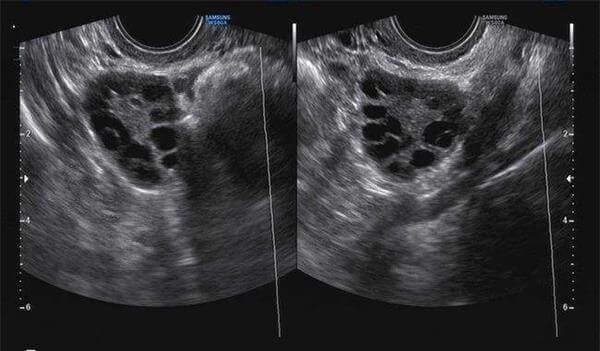

通过B超进行监测卵泡是不能具体查看卵泡情况的,只能够观察卵泡的大小以及数量,并且基础卵泡数量与实际取卵数量会出现一些偏差,这主要是因为并非是每个基础卵子都能够孕育出成熟的卵子,因此就会造成基础卵泡数量和实际获取到的卵泡储量不同,具体相差多少是需要更具患者的卵巢与身体情况进行决定的。

每位女性在做试管婴儿时,都需要进行卵泡监测,但到了实际取卵手术的时候就会发现,最后取出来的卵子数量和基础卵泡数量不一样,少了几个或者更多,这个主要是因为女性患者体内的卵泡发育不均匀或者其他疾病导致的,接下来我们就这一问题进行一个详细的了解。

- 1. 基础卵泡数量与实际取卵数量会有所偏差,而女性当月的基础数量则是决定试管婴儿过程中能够获取的卵子数量的上限;

- 2. 而主要导致这种情况的原因是,卵泡发育不良。女性如果有出现卵巢疾病,例如多囊卵巢综合征、下丘脑-垂体功能异常、内分泌异常等都是可能会导致卵泡发育不良,从而导致基础卵泡数量大于实际取卵的数量;

- 3. 第二个导致这种情况的原因是,空卵泡。这主要是因女性存在卵巢功能衰竭或者卵子发育早期出现闭锁,从而停止了发育,卵泡虽然在激素和药物的刺激下发育成长,但里面其实没有可以用的卵子。

以上两种情况都是导致最后基础卵泡数量大于实际取卵数量的主要原因,建议各位患者在试管婴儿前或者促排期间把自己的身体调整到最好的状态,让自己体内的激素达到平衡,这样才能够得到更多发基础数量,从而获取到更多的卵子数量。